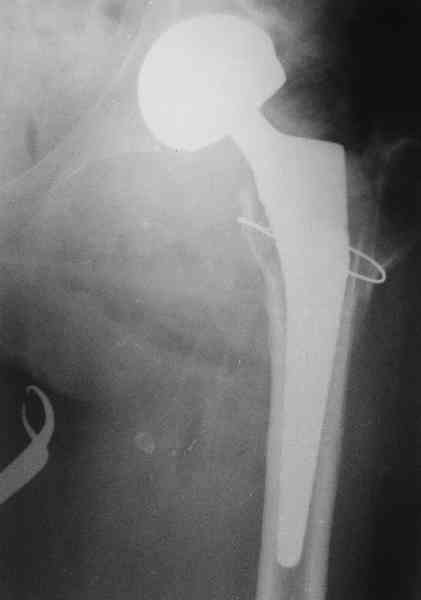

Коллеги, обещанный follow-up.

Больного прооперировали на прошлой неделе (цементный протез, цемент с гентамицином). Использовали задне-боковой доступ. В области перелома подвижности практически не было, так что тему сообщения уместно заменить на "неправильно сросшаяся шейка". И в головке, и во впадине

были значительные дегенеративные изменения, так что ни биполяр, ни остеосинтез тут неуместны (хотя это предлагали в ortopod'е). После релиза удлинили ногу на 3 см. Дальше удлинять побоялись из-за

натяжения седалищного нерва, хотя в принципе можно было бы еще 15-20 мм нарастить. По послеоперационной рентгенограмме анатомическое укорочение порядка 15 мм. Клинически при ходьбе - 4 см, но это за счет перекоса таза.

Dear colleagues,

thanks for all comments you've done on this case.

The patient underwent cemented THR on last week. Postero-lateral approach was used. There was only minimal motion at the fracture site and we had to cut the femoral head with oscillating saw. The femoral head was deformed with it's cartilage completely absent in some areas.

Acetabulum showed gross degenerative changes, especially in superior rim. So I think it was right choice not to do ORIF in this case. After some soft tissue release we've lengthened the leg up to 3 cm. Further lengthening was possible but we stopped at that moment due to tension of n. ischiadicus. Now patient walks with crutches. Leg length discrepancy is about 4 cm due to pelvic tilt (discrepancy on post-op x-ray is 15 mm).